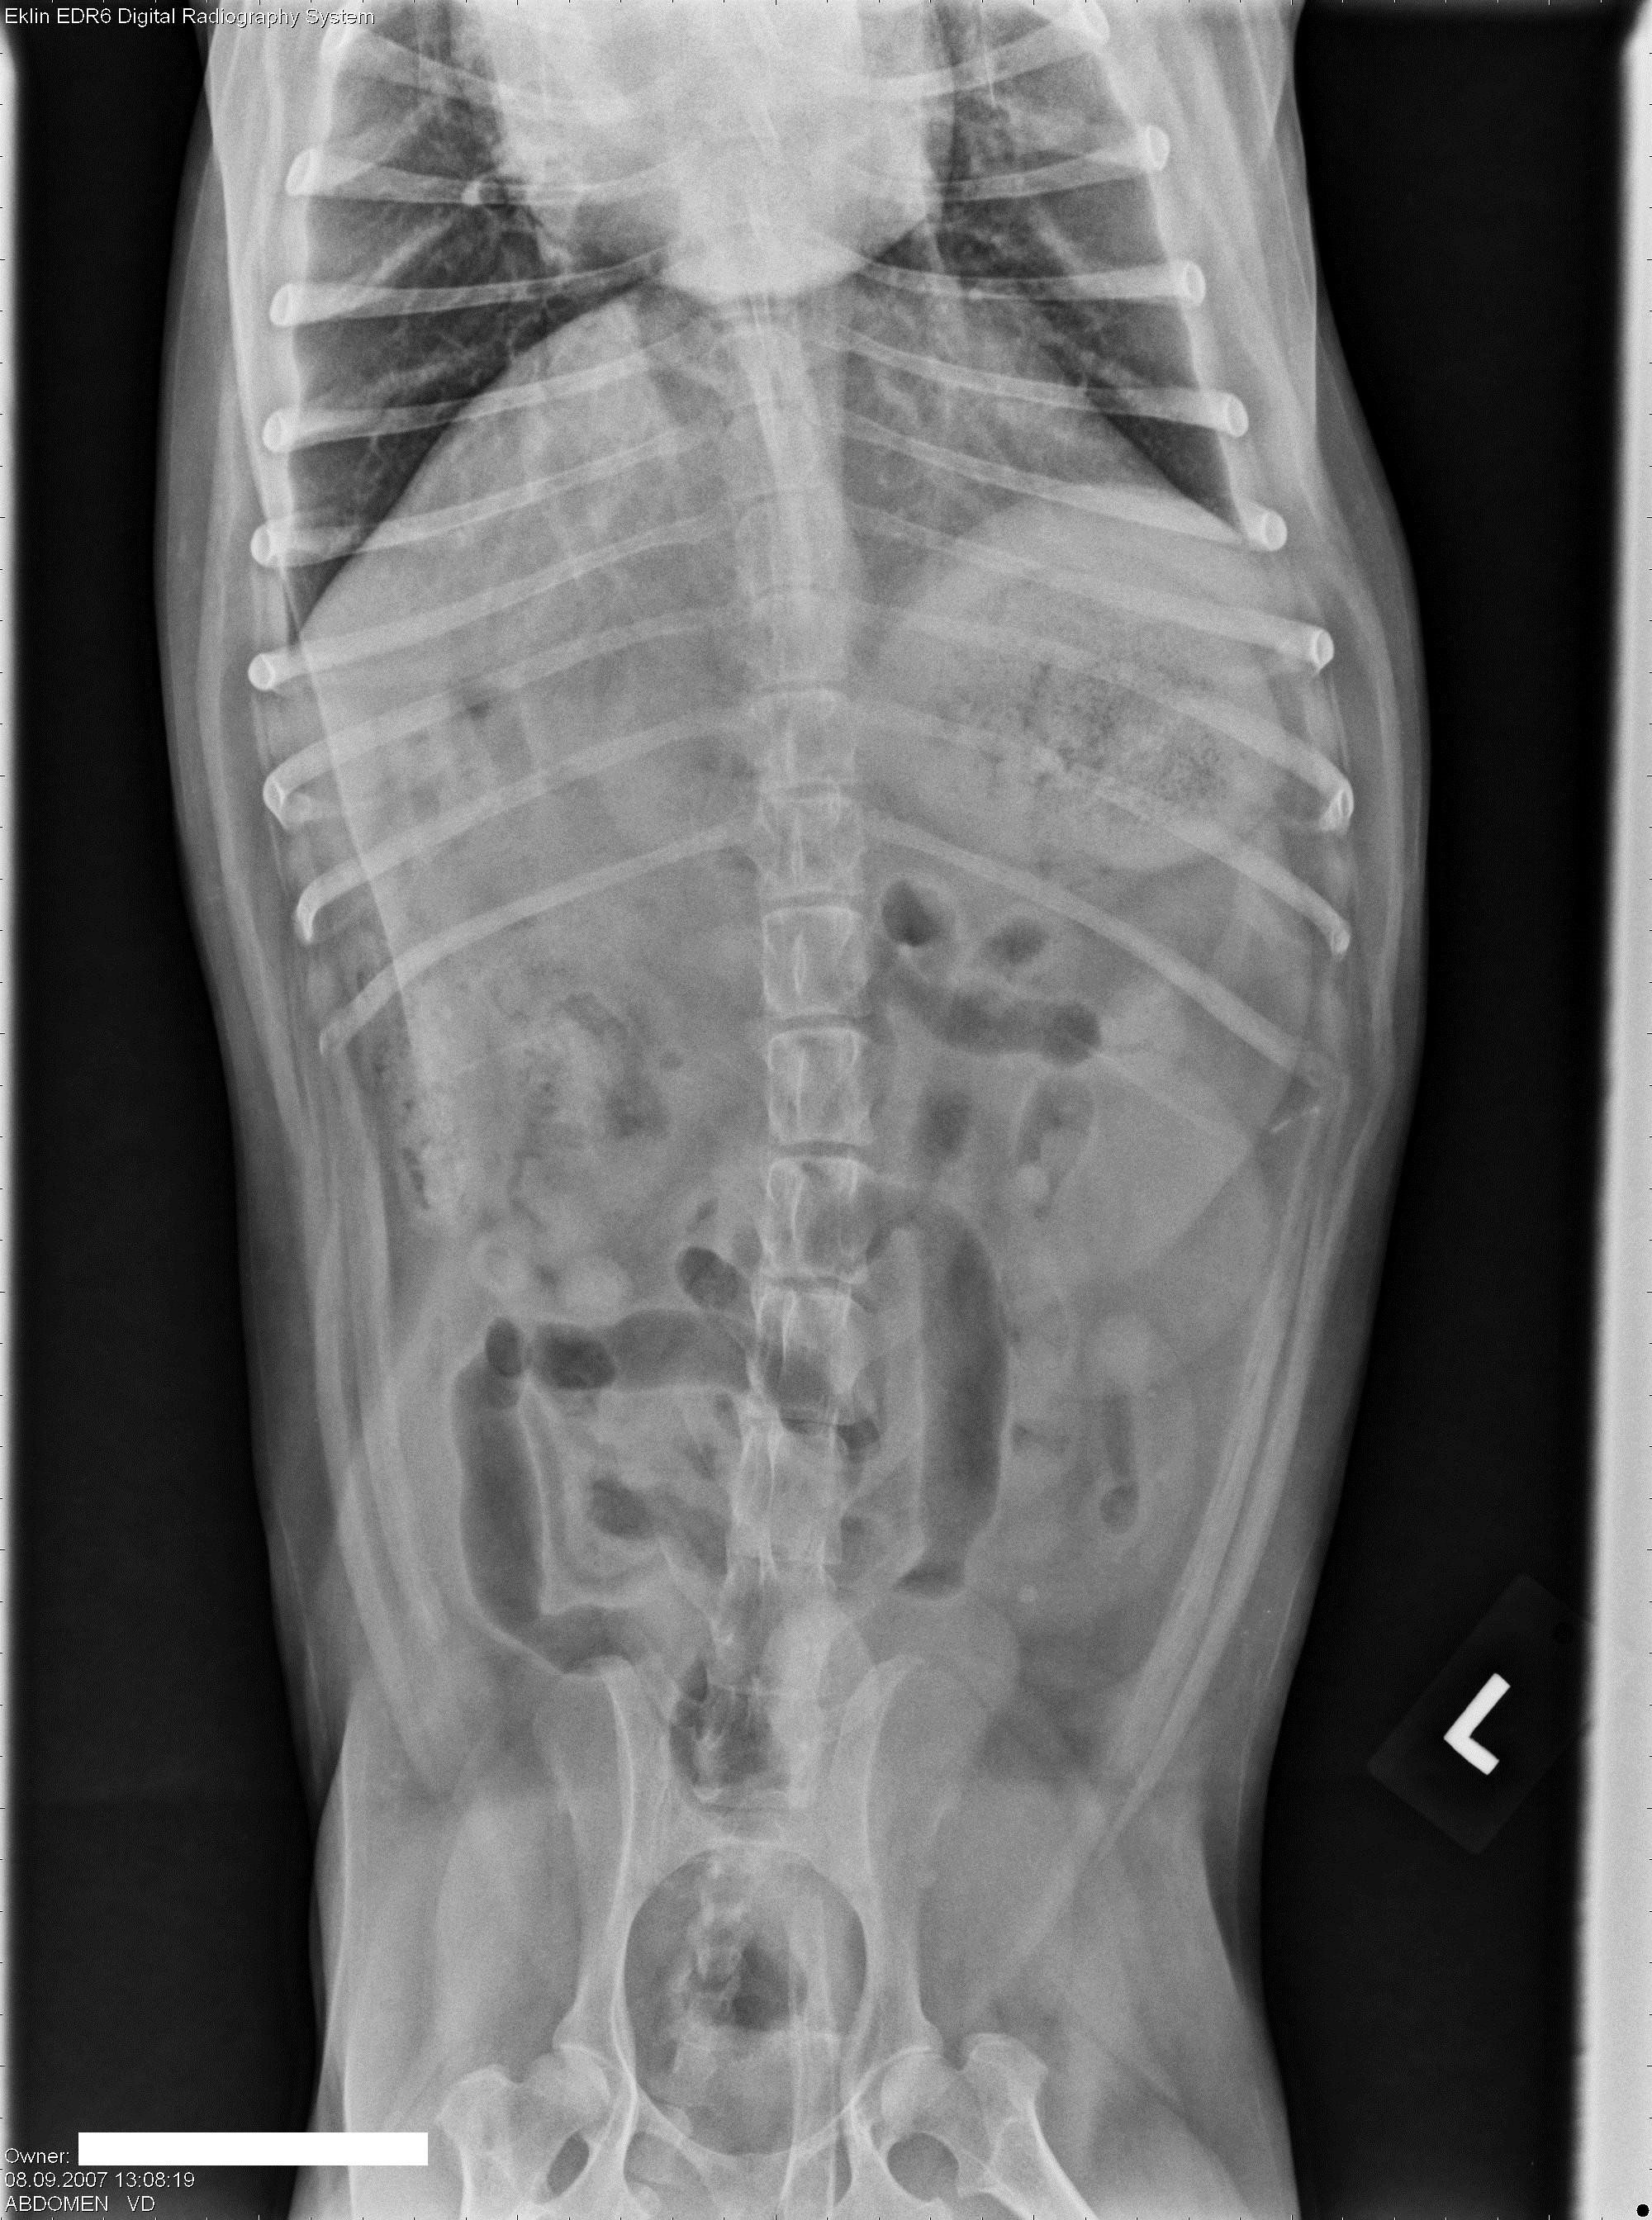

Een 10 jaar oude, mannelijk, gecastreerde hond wordt bij je aangeboden met erge tenesmus.Â

Hieronder vind je 5 Röntgen foto’s thorax en abdomen. Gebruik de pijltjes om erdoor te schuiven, of klik op de foto om te vergroten.